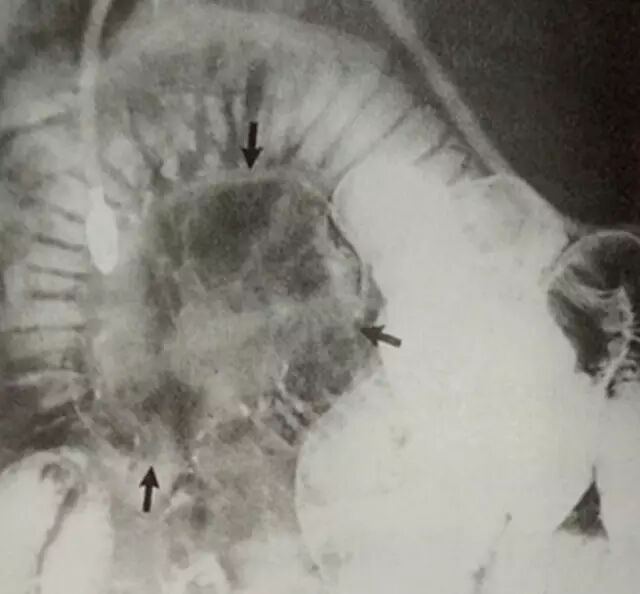

↑图:空肠平滑肌肉瘤